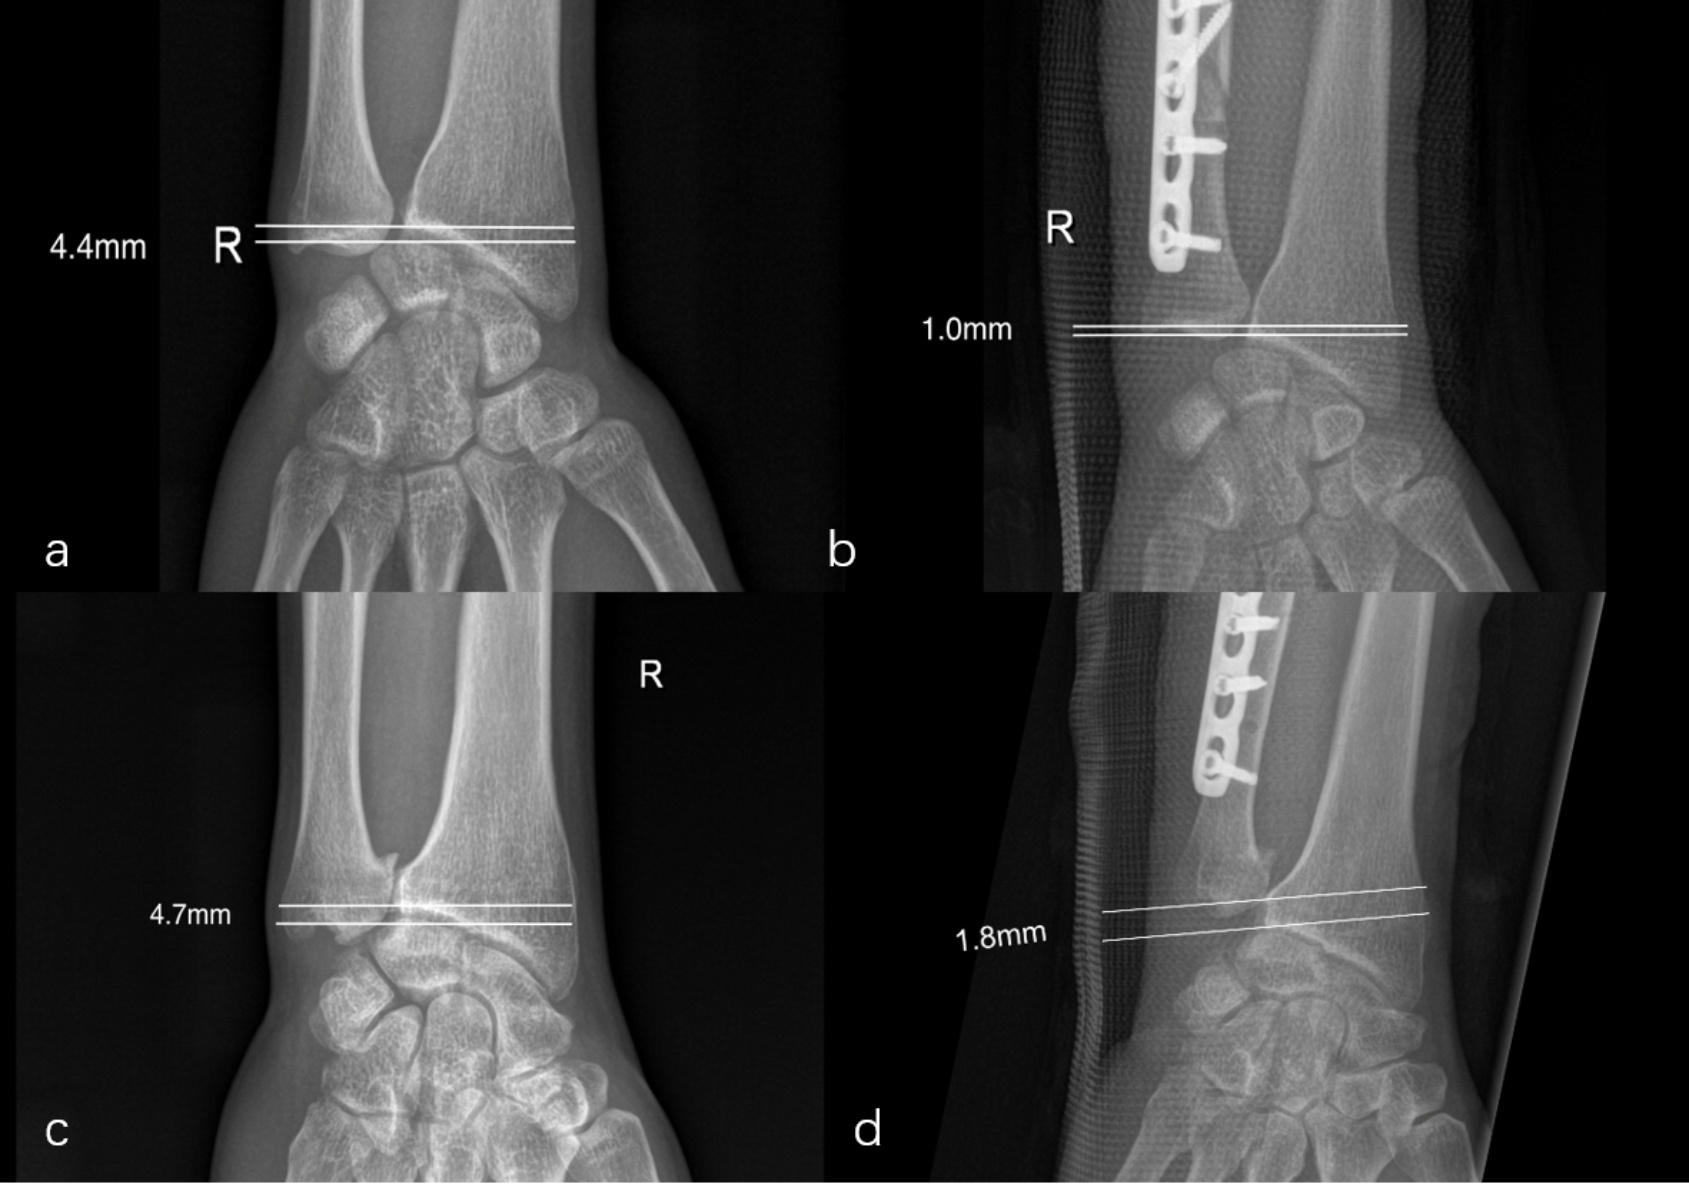

本组17名患者,19例病例,男11例,女6例;年龄介于15~56岁之间,平均38.69岁。其中右侧10例,左侧9例。病程(10.75 ± 4.05)个月。术前腕关节标准位X线片采用Gelberman等[6]平行线测量尺骨变异(图1),以桡骨远端乙状切迹关节面平行线为基准,计算尺骨远端关节面平行线与之的距离差值。经测量,该组均为尺骨正变异。变异值1.6~6.4 mm,平均3.48 mm。术前MRI提示:14例明确TFCC损伤,4例可疑损伤,1例显示不清。

Figure 1. The ulnar variation values measured by the Gelberman parallel line method: comparison before surgery ((a), (c)) and after surgery ((b), (d))

1. Gelberman平行线测量法测量尺骨变异值:术前((a), (c))与术后((b), (d))对比